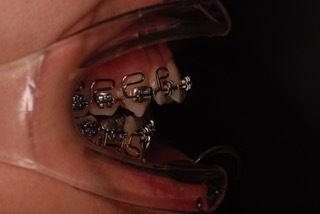

経過をご覧ください。

同じく、矯正器具とゴムを使って改善を図りました。

正面においては、真ん中がぴったりと揃い、前歯も閉じているのが分かります。

側面においては、上の前歯は下がり、下の顎が前方に誘導されているのも確認出来ます。